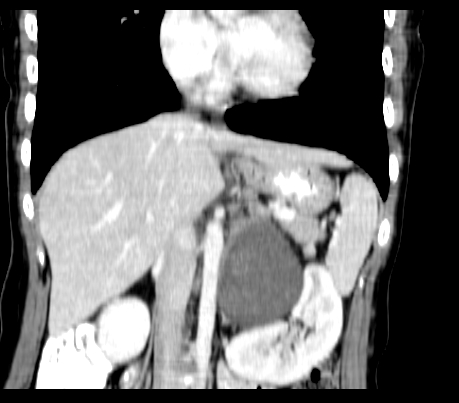

标题: CT23915:女 20岁 全身长疙瘩三年 今日多体位查 看看吧 [打印本页]

标题: CT23915:女 20岁 全身长疙瘩三年 今日多体位查 看看吧

腹部平扫

动脉期

静脉期

延时5分钟

延时10分钟

重建

神经纤维瘤病

支持神经纤维瘤。

支持 神经纤维瘤病。